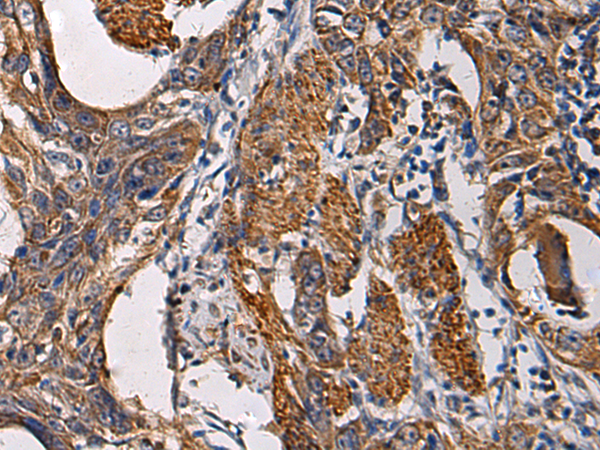

IHC positive control:

Human esophagus cancer and Human breast cancer

IHC Recommend dilution:

50-200